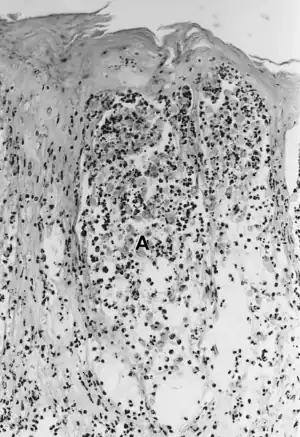

Foot-and-mouth disease - acantholysis in a sample of a skin vesicle: Necrosis of the stratum spinosum can be observed, and keratinocytes floating in the vesicular fluid (spongiosa).